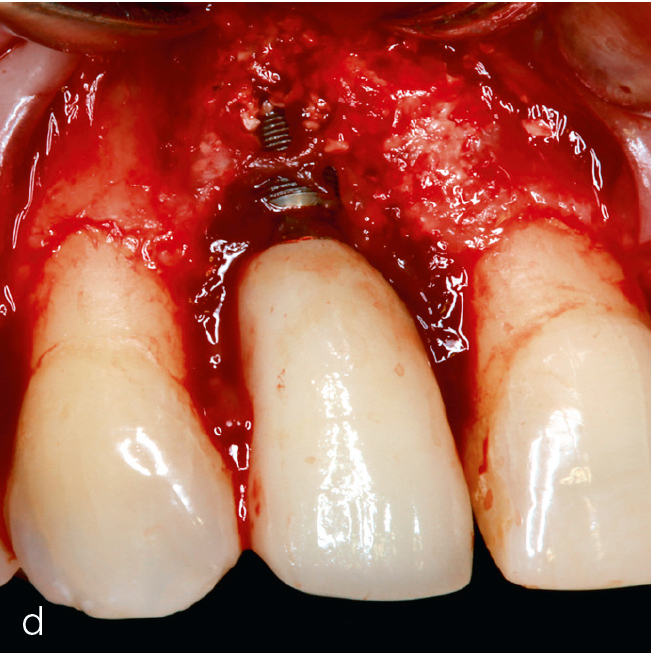

Abb. 3a bis h Falldokumentation mit Zustand nach Implantation und lateraler Augmentation alio loco: a) klinische Ausgangssituation mit Fistelung vestibulär in der Region 12; b) klinische Parameter (PI=Plaque Index 1-3, ST=Sondierungstiefe, MR=Mukosarezession, KM=keratinisierte Mukosa, BOP=Bleeding on probing, SUPP=Suppuration); c) radiologische Ausgangssituation mit initialem periimplantären Knochenabbau; d) operativer Zugang; e) Defektdarstellung nach Entfernung des periimplantären Entzündungsgewebes; f) Defektaugmentation mit einem Gemisch aus Eigenknochen und xenogenem Knochenersatzmaterial; g) Kollagenmembran; h) das aus dem Gaumenbereich entnommene Bindegewebstransplantat (BGT).